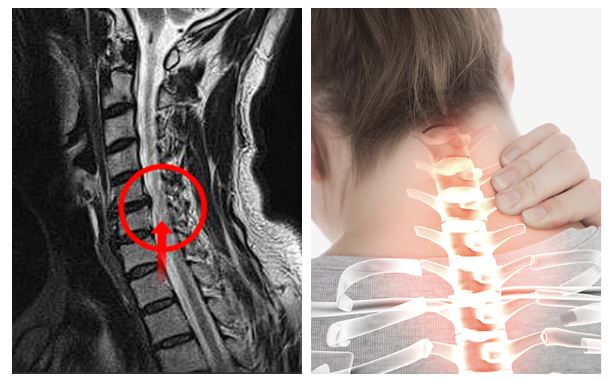

척추에는 뼈의 정렬과 움직임 그리고 안정감을 담당하기 위함으로 지지대 역할을 하는 여러 인대가 존재해요. 전형적으로 척추 전방의 전종인대와 후방의 후종인대를 들 수 있어요. 척추는 목 부위의 경추부터 꼬리뼈 주위 천추에 이르는 33개의 뼈로 되어 있으며 척추관은 척추 가운데 관 형상의 빈 공간으로 척추관 속에는 뇌로부터 팔다리까지 신경이 지나가는 통로라고 할수 있습니다.

목디스크가 생기면 경추 사이 디스크가 밀려나오며 팔이나 손가락으로 걸치는 신경을 눌러서 억누르게 됩니다 하더라고요. 압박증상으로 말미암아 해당 부위의 감각이 둔해지며 척추가 불안정하게도면 부근에 자리한 관절까지 영향을 미치게 돼 바랍니다. 그러면서 어깨 통증도 나타나게 되지만 이러한 어깨 통증을 느끼시면 오십견 등의 어깨질환과 혼동할 수 있다고 하지만 머리 뒤에 손을 얹는 동작을 하면 통증이 감퇴하는 경우도 있어서 목디스크로 의심을 해보시고 진료를 받아보시는 걸 권장드립니다.

목의 디스크가 손상이 일어나서 부근 신경을 자극하여 심각한 통증을 같이할수 있는데요 통증은 상식적으로 목의 한쪽 면에 유발되며, 어깨나 팔까지 타나날 수 있습니다.

목디스크는 경추 디스크의 이색적인 위치에서 벗어나서 신경에 압박을 가할 때 일어나는 질환이고요. 이로 말미암아 근육에 약화가 생겨날 수 있기도하고, 손의 근육이 약해지거나 일부 거동이 억제될 수 있다고 합니다. 이러한 증상은 보통 압박이 있는 신경이 어떠한 부위에 위치하는지에 따라 변화합니다.